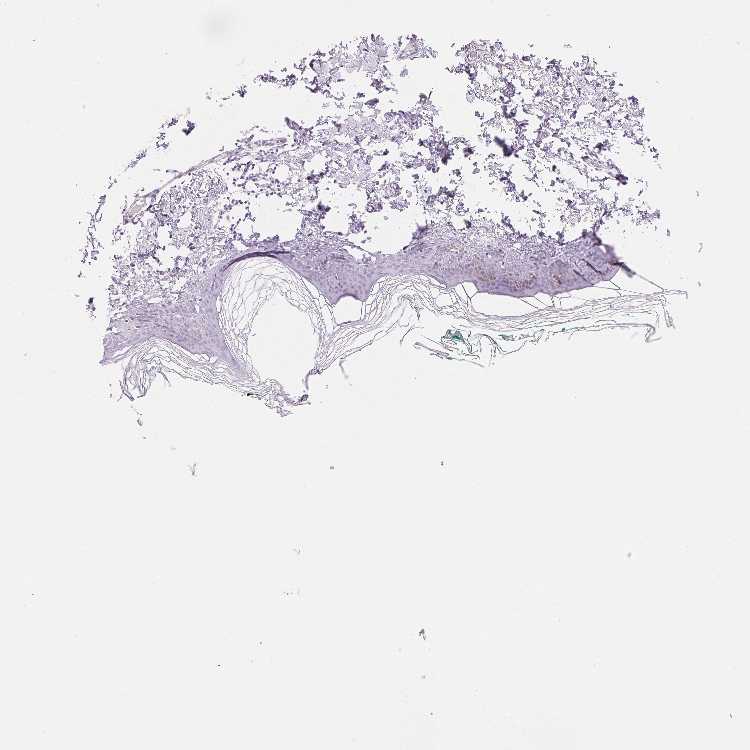

SKIN 1 - Antibody stainingi

Antibody staining in the annotated cell types in the current human tissue is reported as not detected, low, medium, or high, based on conventional immunohistochemistry profiling in selected tissues. This score is based on the combination of the staining intensity and fraction of stained cells.

Each image is clickable and will lead to virtual microscopy that enables deeper exploration of all samples and also displays staining intensity scores, fraction scores and subcellular localization as well as patient and tissue information for each sample.

Antibody HPA056020

Langerhans Not detected

Fibroblasts Not detected

Keratinocytes Not detected

Melanocytes Not detected